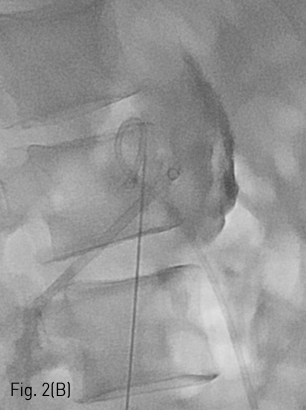

Fig 2B

(A-B) Chiba needle was advanced under fluoroscopic guidance until entrance into the renal pelvis.

환자는 왼쪽 신장의 isolated calyx에는 8.5Fr. drainage catheter가 insertion 되어 있고 left renal pelvis에는 double J stent가 insertion 되어 있는 상태로 prone position을 취하였다. 기존의 drainage catheter에 0.035inch 유도 철사(Terumo, Tokyo, Japan)를 insertion 하고 catheter는 제거한 후 8Fr. Sheath(Boson, Shrewsbury, USA)를 삽입하였다. 조영제(Visipaque, GE healthcare, Chicago, USA)를 주사하여 tubogram을 시행하였고 isolated calyx 와 콩팥깔때기와의 연결성은 없었다. (Fig.1B) 초음파 유도 하에 21G 천자바늘(Cook, Bloomington, USA)로 isolated calyx를 천자하고 X선 투시하에 천자바늘을 콩팥깔때기에 insertion 되어 있는 double J catheter를 향해 진입시켰다. (Fig. 2A, B) 천자바늘의 속심을 제거한 후 X선 투시하에 조영제를 주사하여 isolated calyx를 지나 콩팥깔때기가 천자된 것을 확인하고 0.018inch 유도 철사(A & A, Gyeonggi, Korea)를 넣었다. (Fig. 2C) 이후 천자바늘을 제거하고 단일 막대 접근 장치(yellow sheath; A & A, Gyeonggi, Korea)를 이용하여 접근로를 확보했다. 유도 철사와 metal stiffening inner cannula를 제거하고 0.035inch 유도철사(Terumo, Tokyo, Japan)를 넣고 6mm x 4cm balloon(Boson, Shrewsbury, USA)을 이용하여 isolated calyx와 콩팥깔때기 간 neoinfundibulum 을 재건하였다. (Fig. 2D) 삽입되어 있는 유도 철사를 통해 isolated calyx, neoinfundibulum 그리고 콩팥깔때기를 차례로 통과하도록 10.2Fr. nephrostomy catheter(Cook, Bloomington, USA)를 위치시켰다. (Fig. 2E) 4일 후 기존의 10.2Fr PCN catheter insertion site를 통하여 10Fr sheath(Terumo, Tokyo, Japan)를 insertion 한 뒤 0.035inch 유도철사(Terumo, Tokyo, Japan)를 방광까지 진입시킨 뒤, 26cm 7Fr double J stent(Boson, Shrewsbury, USA)의 원위부는 방광에 위치시키고 근위부는 isolated calyx에 위치시켰다.(Fig. 3) 이후 isolated calyx로의 접근로에는 10.2Fr. nephrostomy catheter(Cook, Bloomington, USA)를 삽입하고 시술을 종료했다.